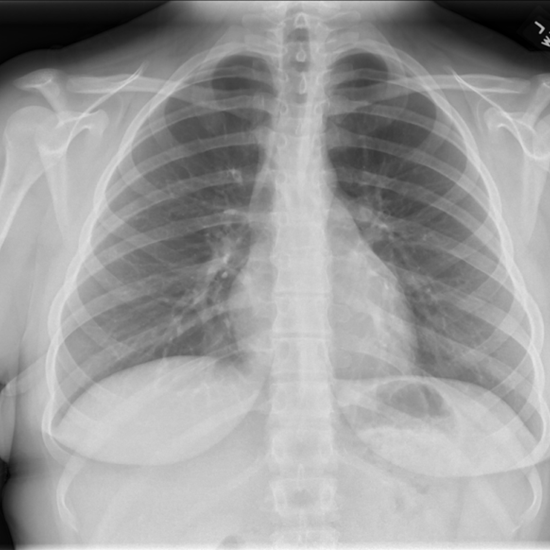

PA/lateral projection is the standard used for most patients who are ambulatory and able to stand. In this view, the mediastinum should have a normal width and a good inspiratory effort should results in full diaphragm expansion.

PA Projection – Normal Mediastinum and Good Inspiratory Effort